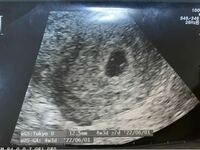

妊娠5週目で心拍確認。 高温期26日目 (排卵チェック済み)にて受診し、胎嚢を確認できました。 さらに、私には分からなかったんですが (エコーの画面が遠くて)、医師は元気な心拍も確認できたと言い、母子手帳発行に必要な用紙を貰って帰ってきました。 次の受診は4週間後です。 5W6Dでも心拍確認できる場合もあるって事は知っていますが、こんなに早い段階で挙句、「来週(6w5d)心拍確認できなかったら育ってないことになります」と素っ気なく言われました。 泣きそうでしたが、来週の診察で心拍が確認できることをイメージして乗り切ります 無事に来週心拍確認できるよね、ベビちゃん! ちなみに、3/13(D1)からD16で排卵して計算しています。D1からの計算だとこのエコーは6w0dになります心拍確認したらひと安心って本当?妊娠何週でわ 妊娠がわかってうれしいけれど、赤ちゃんの心拍が確認されるまでは不安がいっぱい。心拍確認の意味や、流産の可能性についてなど、妊娠超初期の心拍確認にまつわる疑問にお答えします。 Amazoncojp

心拍確認がいつ頃できるかについては、 早い人だと妊娠5週 でできる人もいますが、 大体6~7週頃に心拍確認ができる人が多い ようです。 遅くても8~9週目までに確認できます。 専門家も以下のようにいっています。 心拍が見え始めるのは、早い人で5週 妊娠5週と5日で心拍が確認できることってありますか? 今日病院のエコーで、「心拍が確認できますね。ぴょこぴょこ動いているのがかすかにわかりますね~。 」と言われました。 まだ妊娠5週と5日ですが、心拍が確認できることってあるんでしょうか? 心拍が確認できるのは大体6週~7週と聞いていたので、嬉しい反面、少し早い気がするのですが。 ちなみに 5週1日の胎嚢確認後、心拍確認のために6週0日に再び産婦人科を訪れた時のまとめです。心拍確認や、内診の様子、エコーを入れる際の痛みはどうにかならないか検討したことを書きました。 漫画 妊活 育児 お買いもの 家計簿 お問い合わせ プライバシーポリシー 初めての妊娠96週

おなまえ Kelly ねんれい 33 妊娠週 5w6d これは私の場合、5週で胎嚢5ミリ、 6週で胎嚢124ミリ 胎芽1ミリ(心拍微弱確認)、 7週で出血が始まり完全流産でした。 初めての妊娠だったのですが、つわりは最初からあまりなく、またお腹が頻繁に張っていたように思います。 5週の時点で胎嚢が子宮のかなり低い位置にあると言われ、 無事に 妊娠5~7週 胎嚢&心拍確認とつわり テーマ: 妊娠中 こんばんは! 前回の記事コメントのお返事 し終わりました 遅くなって失礼いたしました 妊娠中のこともボチボチ書くことに